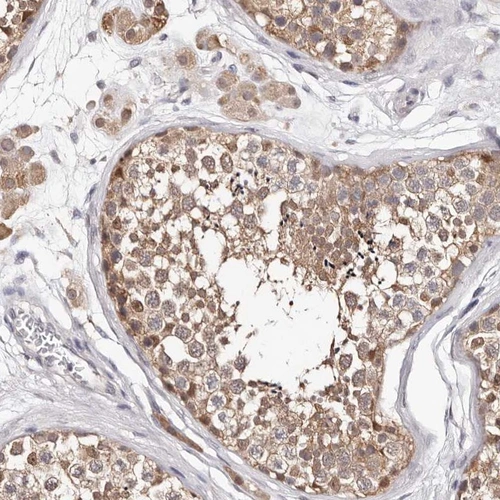

Immunohistochemical staining of human testis shows moderate cytoplasmic positivity in seminiferous ducts.